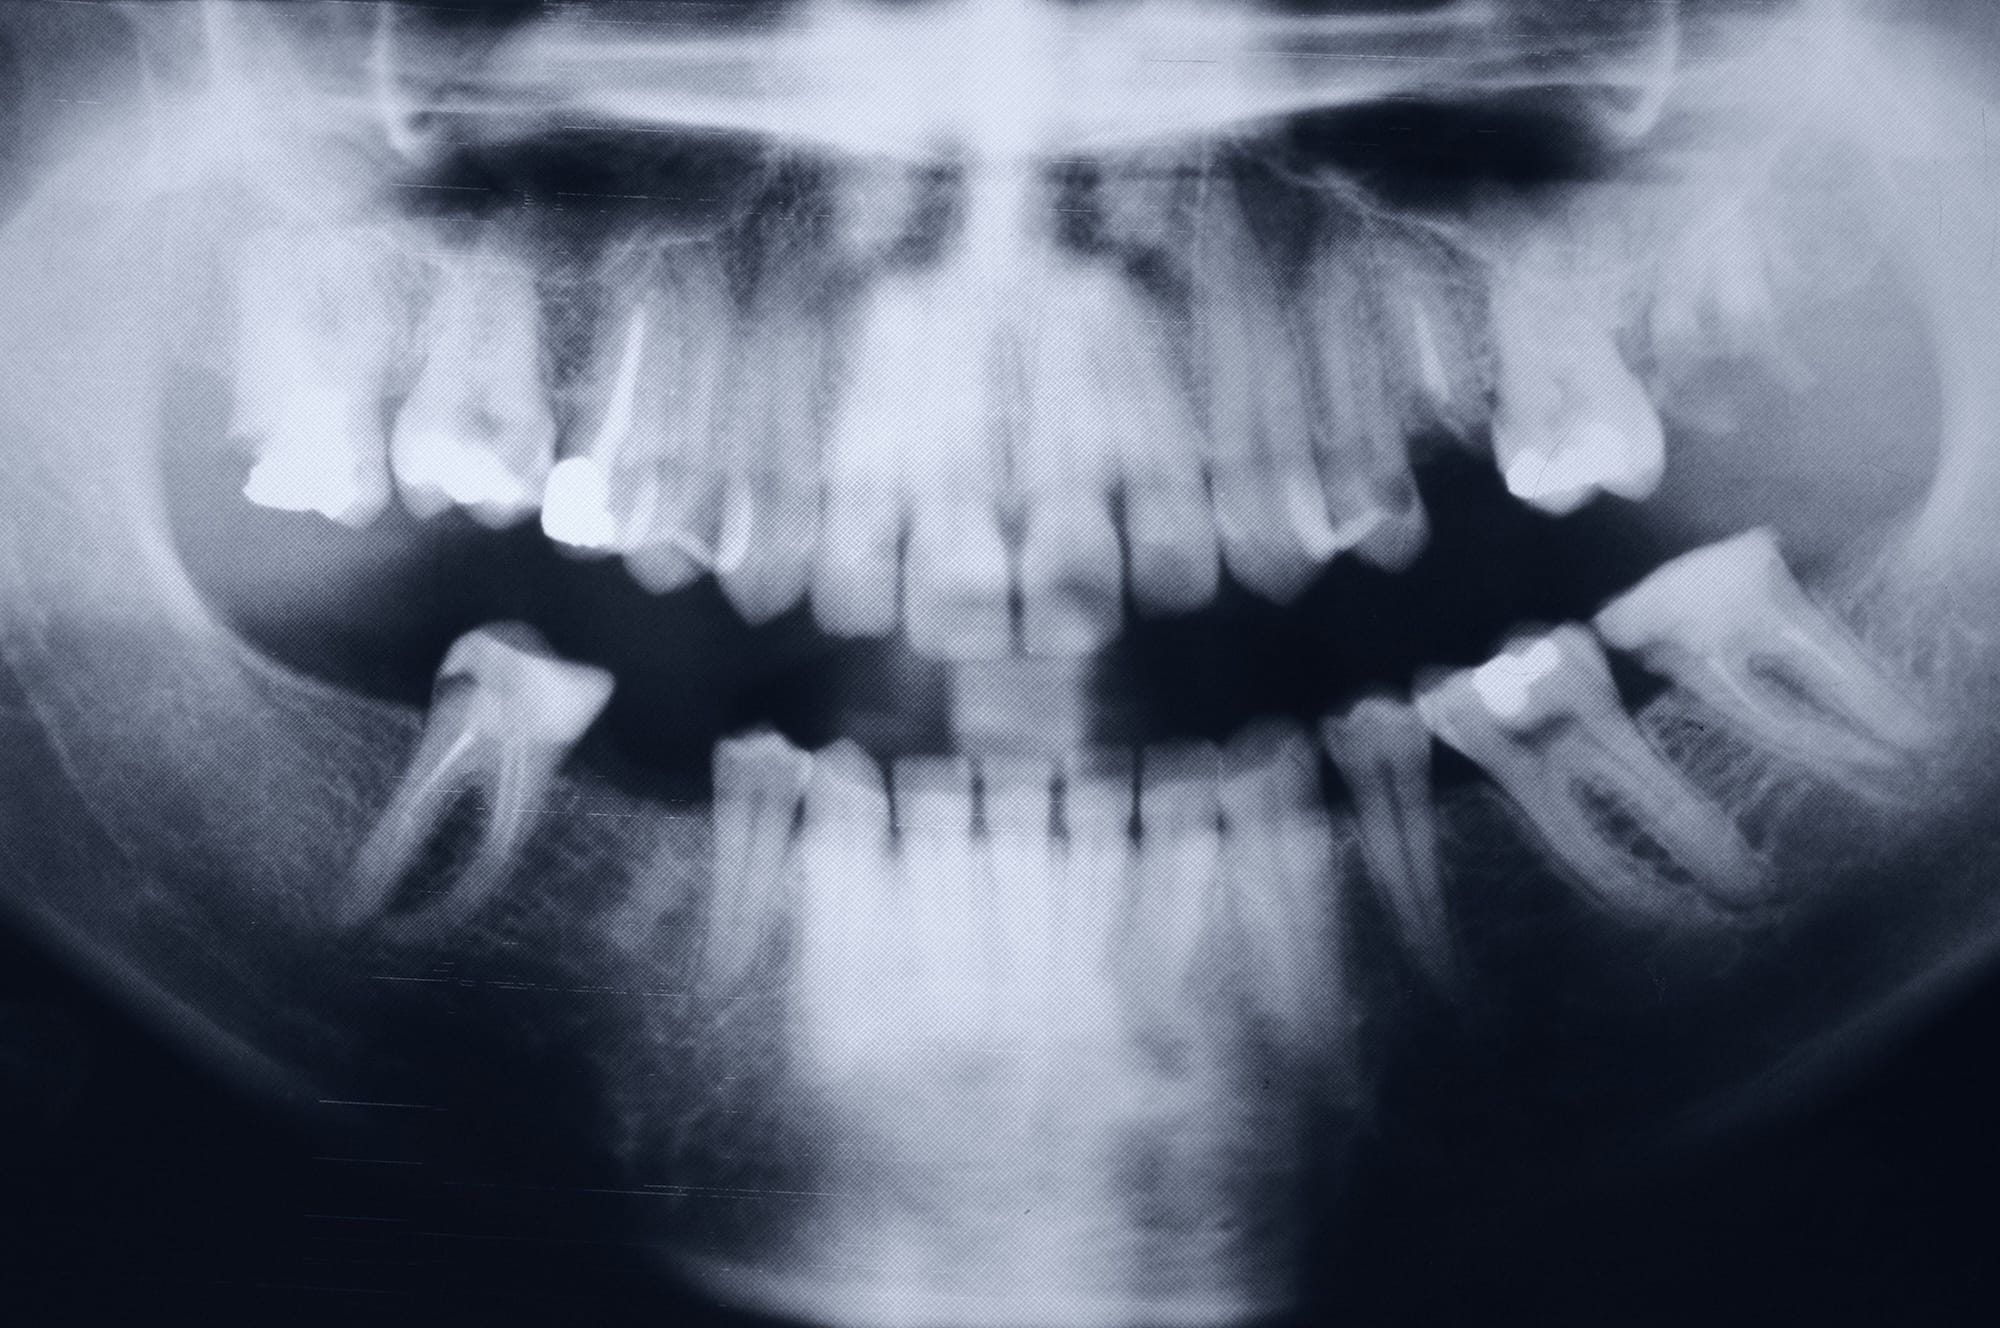

Röntgenaufnahme eines Gebisses: Schwarz-weiß Bild zeigt Zähne, Kieferstruktur und Zahnwurzeln zur Diagnose beim Zahnarzt.

Weisheits­zahn­entfernung

Schonend und sicher – auch unter Narkose

Weis­heits­zähne treten erst spät auf den Plan, meist nach dem 18. Lebens­jahr. Weil der Kiefer heute oft zu wenig Platz für sie bietet, wachsen Weis­heits­zähne oft schräg oder bleiben im Knochen verborgen. Das kann Schmerzen verur­sa­chen, die umlie­genden Zähne verschieben und Karies oder Entzün­dungen begüns­tigen. Ob eine Entfer­nung sinnvoll ist, zeigen eine gründ­liche Unter­su­chung und das Rönt­gen­bild. Bei YASMILE in Kirn nutzen wir dafür digitales 3D-Röntgen (DVT), das die Lage des Zahns und der umge­benden Nerven­bahnen genau darstellt.